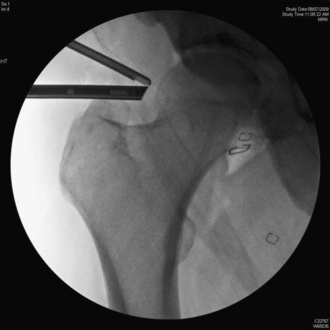

Although many surgeons prefer to perform peripheral compartment arthroscopy with the hip flexed 20 degrees to 45 degrees to further relax the anterior capsule, I prefer to perform cam surgery decompression with the hip in neutral flexion and extension. When the extremity is in neutral flexion and extension, it is easier to get a truer fluoroscopic image, because the fluoroscope beam can be made perpendicular to the axis of the femur (Figure 19-14). Because fluoroscopy beams diverge, there is inherent distortion, which would be magnified if the central fluoroscopic beam is not perpendicular to the proximal femur; this may result in inadequate or excessive bony resection. While there are benefits to peripheral compartment arthroscopy in the neutral flexion-extension position, the trade-off, which the author accepts, is that it is necessary to perform a partial capsulectomy of the anterolateral capsule to allow for adequate visualization.

Figure 19–16 Fluoroscopic image of the trocar in the anterolateral portal and the shaver at the location of the maximal deformity.